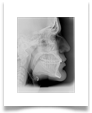

Nel nostro Studio impieghiamo un sistema radiografico computerizzato, il Vista Scan Plus della Dürr che consente di ottenere immagini di alta qualità (vedi confronto analogico/digitale) con dosi radiogene sensibilmente più basse per il paziente.

Con Vistascan Plus siamo in grado di ottenere, nel giro di pochi minuti, tutte le immagini che ci servono per un corretto ausilio diagnostico: bitewing, endorali, ortopantomografie, teleradiografie.